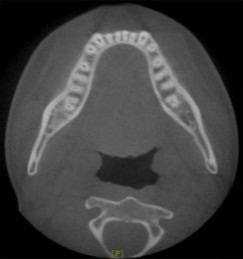

放射检查:一般包括X线头影测量片、曲面体层片和CBCT(锥束CT)。有时还包括其他放射检查,比如螺旋CT等。通过放射检查,医生可以看到骨骼及牙齿的形态、位置及发育状况,以及是否有牙体、根尖周、牙周疾病等,从而评估是否需要正畸治疗、进行何种治疗。

(摘自“第三章第一节正畸的基本知识”)

头影测量片(上)、曲面体层片(中)和锥束CT(下)